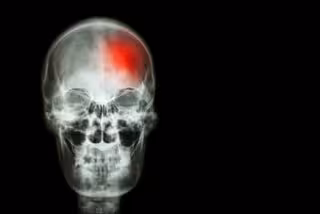

Ictus, cerebro, cerebrovascular

GETTY//STOCKDEVIL